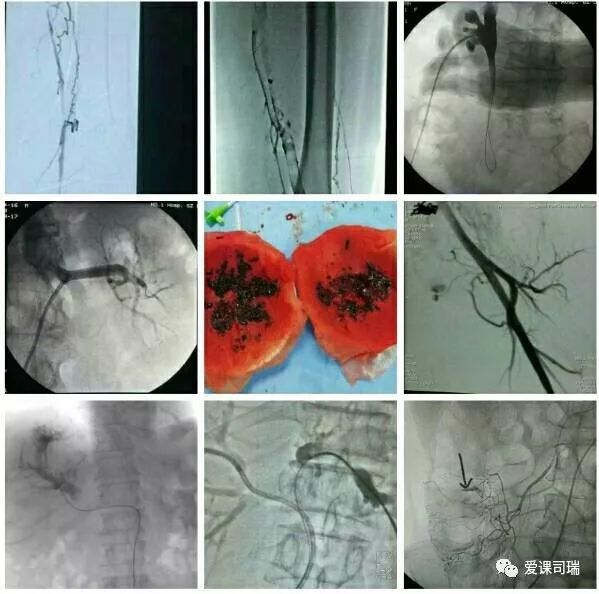

1.有影像设备的引导:在能够“看穿身体”的影像设备帮助下,不需要切开人体,就能看到体内脏器和病变,实现“可视化”。

3.诊断与治疗相融合:介入医生能够通过影像设备直接看到病变,疾病的诊断就很容易明确,随即又可立刻转入治疗过程,实现“诊断治疗一体化”或“诊治一条龙”。整个过程都看得见,治疗过程中又可继续诊断,如果判断效果还没有达到预期,立即追加治疗也非常方便。

概括地说,介入诊疗有以下优势: 1.可以远道施术:借助于导管等器材,可以从对病人最有利、远离病变的部位入手,将治疗器材送达病变局部,再施行精细的治疗。比如,头部有病,我们可以方便地从大腿跟部进管,经血管插管到头部去,从而避免直接切割或穿刺头部。 2.创伤轻微,容易耐受:借助于影像设备这“第三只眼睛”的引导,无须开刀即能清晰显示病变部位,从而进行准确的治疗操作。 3.可重复性强:由于创伤小,不会造成局部的粘连和组织缺损,因而可以多次反复地进行治疗,直到病变完全康复为止。 4.定位准确:有影像设备作实时的引导和监控,没有视觉盲区,因而可以“指哪打哪”。 5.疗效高、见效快:对很多病变可以起到“立竿见影”的效果。 6.并发症发生率低:也就是说安全性高,由上述多种优势的综合作用所致。 7.方便联合应用多种介入技术:介入诊疗技术种类繁多,各有特色和优势,可以方便地联合应用,取长补短,从而进一步增强治疗效果。

在影像设备引导下实施操作是介入诊疗的鲜明特色,故影像设备不可或缺。目前最常用的介入引导设备是DSA机(见下图)。B超、CT、MRI也可引导介入,在定位穿刺、肿瘤消融等方面也各具优势。